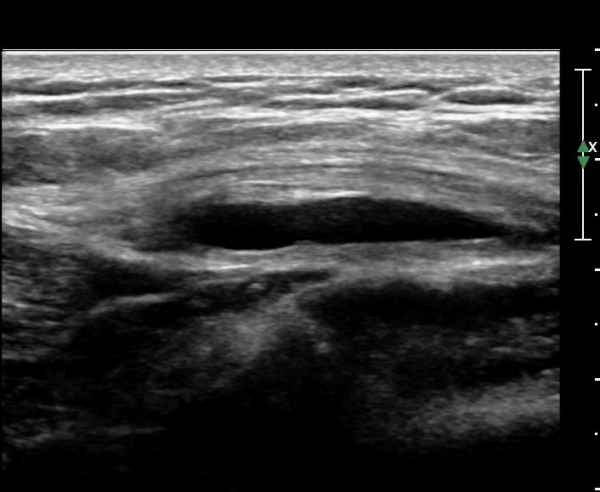

ÃÊÀ½ÆÄ °Ë»ç

´ëÀüÀÚ µÚÂÊ È¾´Ü¸é°Ë»ç¿¡¼­ ÁߵбÙÈûÁÙ°ú Àå°æÀÎ´ë »çÀÌ¿¡ ·®ÀÇ ¼ö¾×Àú·ù°¡ °üÂûµÇ°í(»çÁø 1)